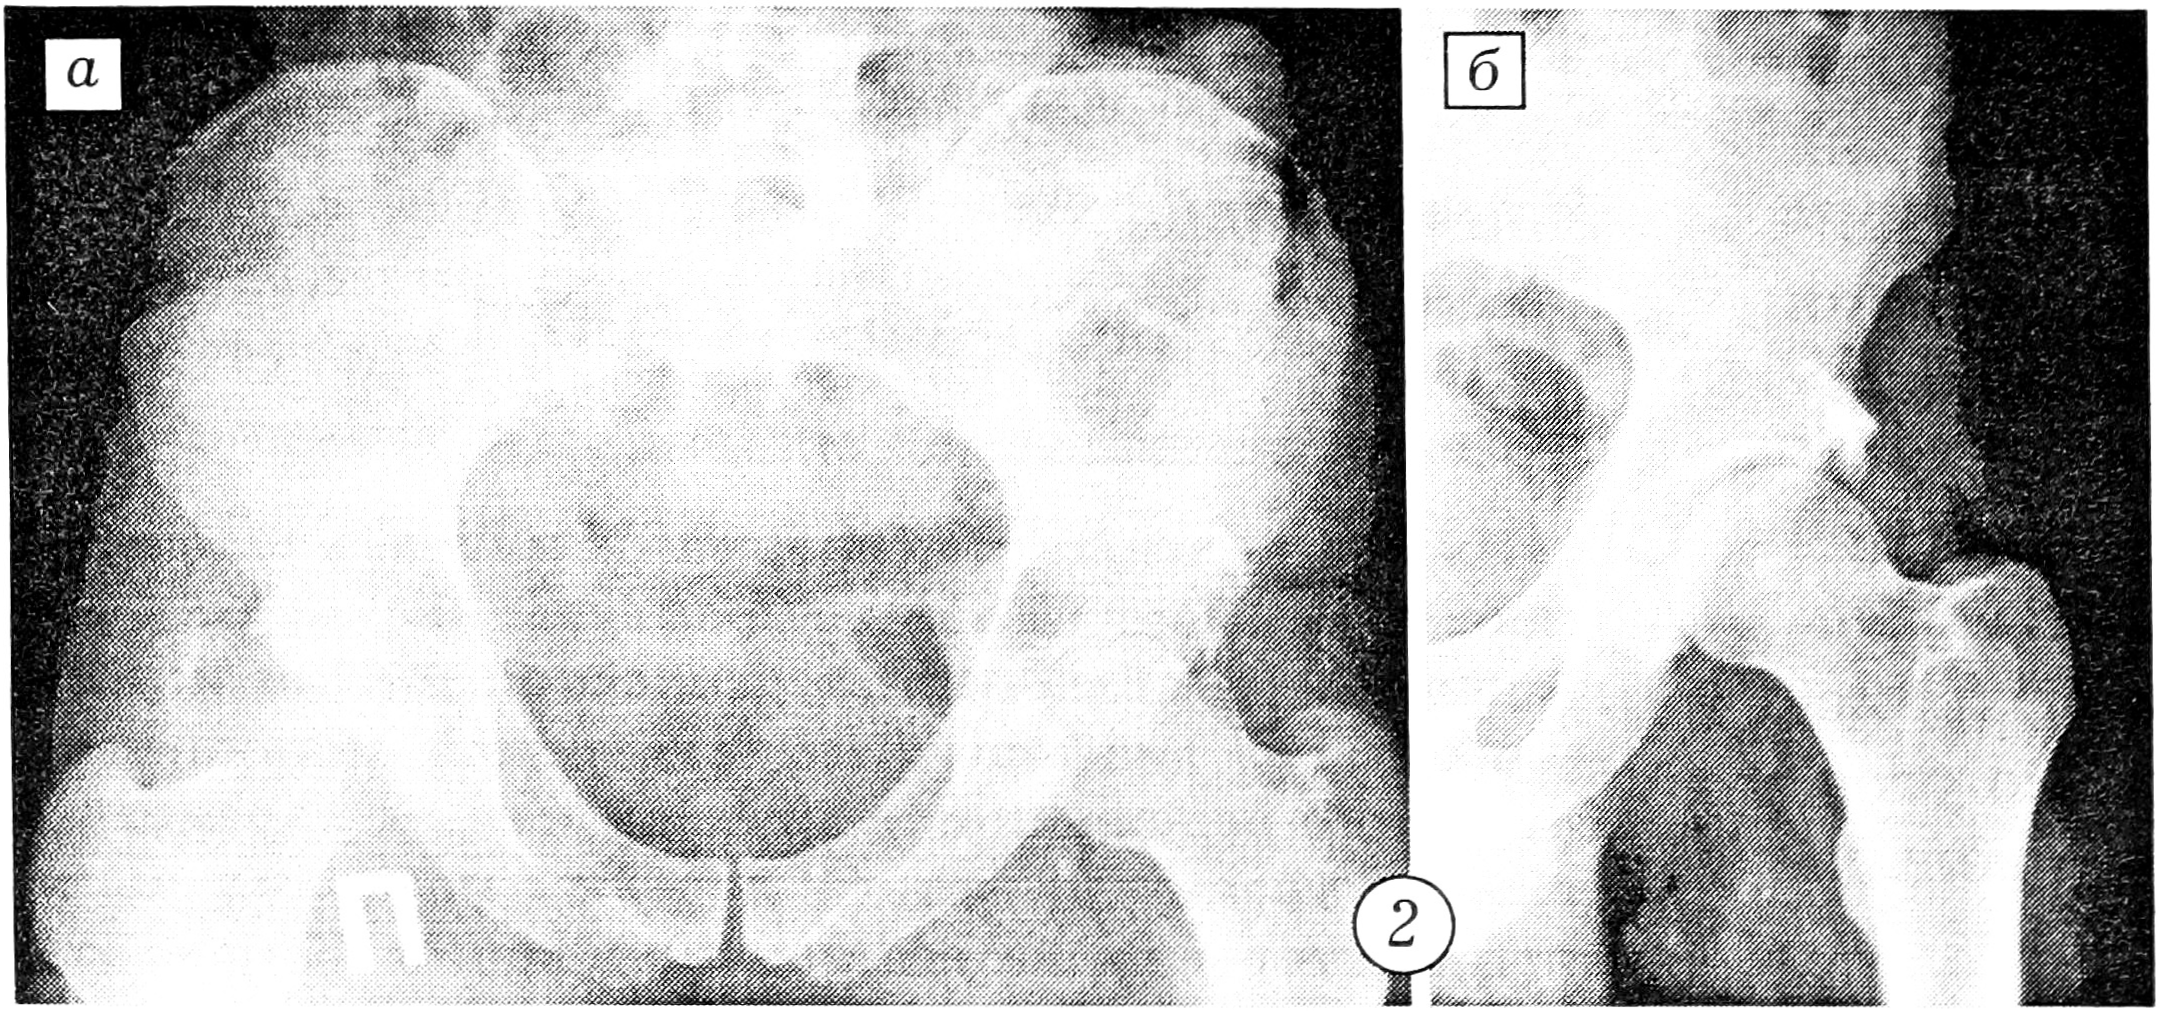

Больной Г., 36 лет, 27.02.95, находясь за рулем автомобиля, попал в автоаварию. Доставлен в больницу по месту получения травмы. При поступлении поставлен диагноз: закрытый вывих левого бедра, перелом вертлужной впадины. Предпринята попытка вправления бедра. После улучшения состояния больного он 1.03 переведен в клинику травматологии ЦИТО. При поступлении проведена рентгенография таза в стандартной переднезадней и запирательной проекциях (рис. 2). Выявлен оскольчатый перелом задневерхнего отдела вертлужной впадины, заподозрено наличие внутрисуставных отломков. С целью уточнения диагноза проведена компьютерная томография тазобедренного сустава. Подтвержден оскольчатый перелом задневерхнего отдела левой вертлужной впадины и, главное, в полости левого тазобедренного сустава выявлены свободный костный фрагмент кортикальной плотности, расположенный в центральном отделе впадины, и несколько более мелких свободных внутрисуставных тел (рис. 3). С учетом характера перелома и внутрисуставной интерпозиции отломков больному 15.03 произведена операция. При ревизии левого тазобедренного сустава в области крыши вертлужной впадины обнаружен фрагмент размером 4,5×5,0×1,5 см с участками хрящевого покрытия и фиброзной губы, смещенный краниально и ротированный кнаружи. После выведения головки бедра из впадины в суставе обнаружены костный фрагмент размером 2,5×1,0×0,8 см из губчатой и компактной ткани и два кортикальных чешуеобразных фрагмента размером 0,7 и 0,5 см. Все костные фрагменты удалены из полости сустава. Сустав промыт. Головка бедра вправлена. Произведена репозиция заднего края вертлужной впадины, фрагмент фиксирован двумя винтами с шайбами. Движения в суставе в полном объеме. Остеосинтез стабильный. Заживление раны первичное. Отдаленный результат хороший.

Рис. 3. Аксиальные компьютерные томограммы таза больного Г.